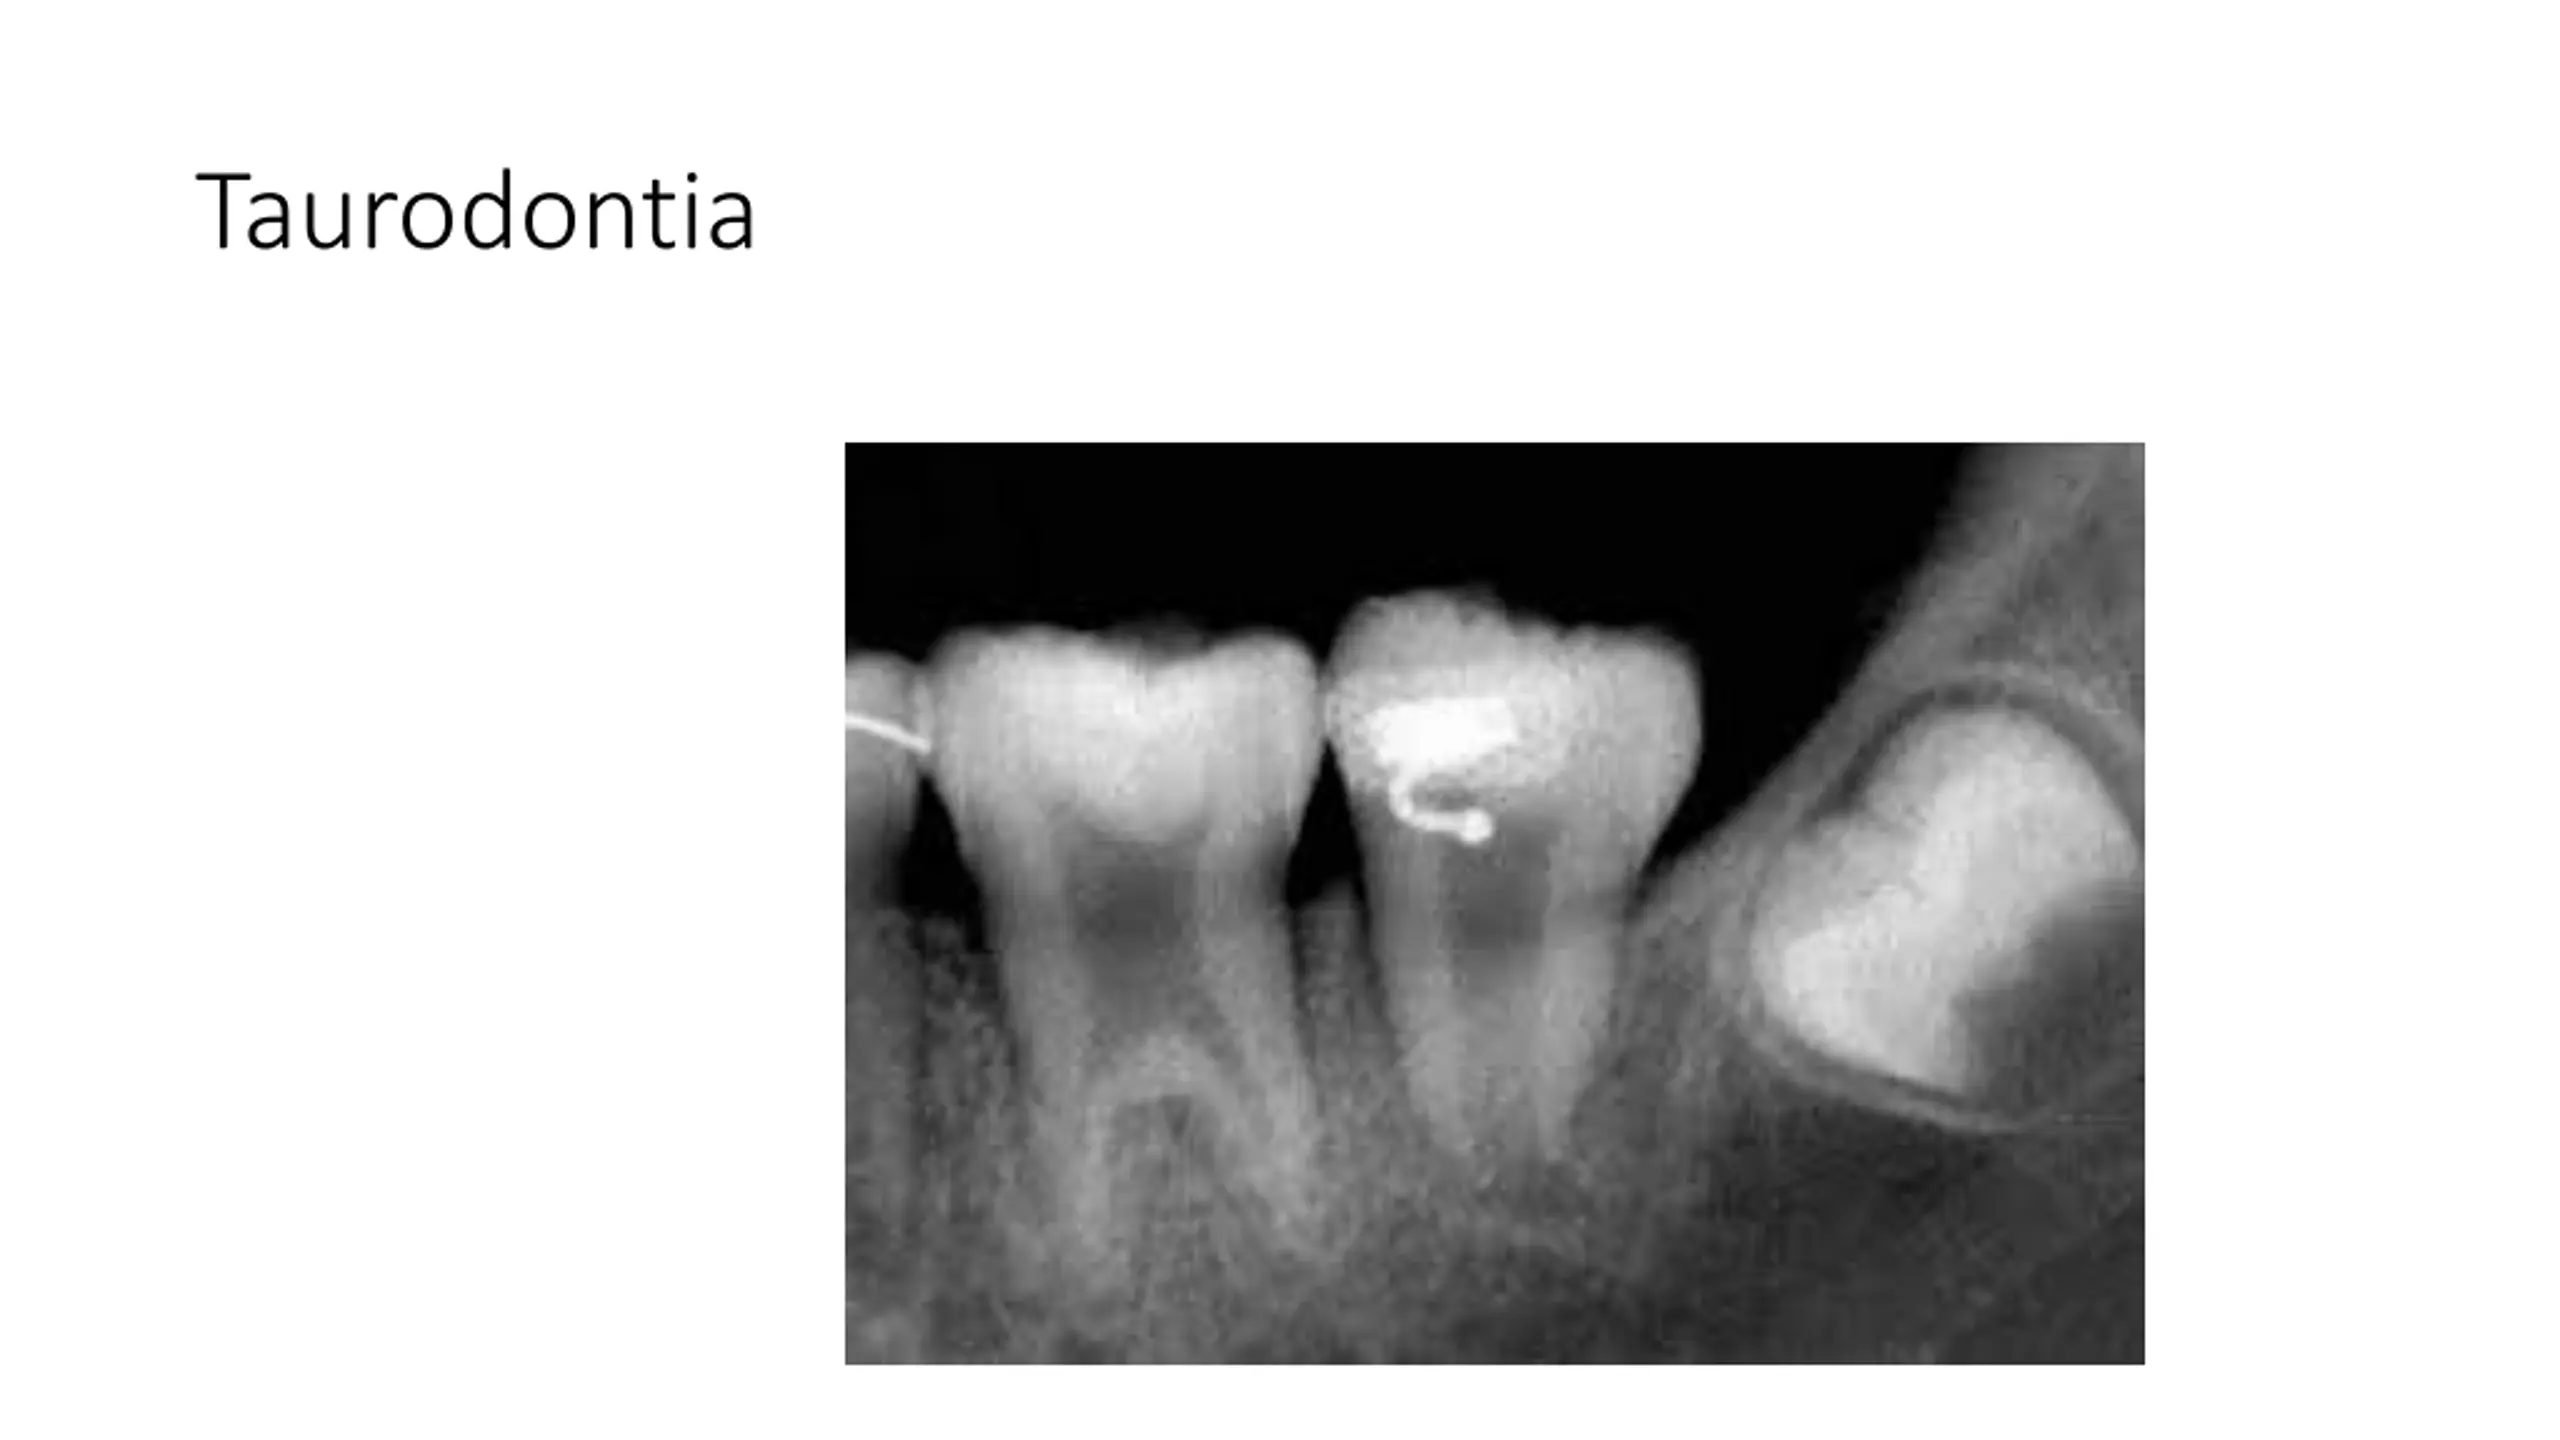

True Anodontia, Partial True Anodontia, Partial False Anodontia, Mesiodens/Supernumerary, Microdontia, Marcrodontia, Gemination/Right Fusion/Left, Peg-Lateral, Fusion Two Roots/Two Crowns, Dens in dente, Dilaceration, Concresences, Taurodontia, Hypercementosis, Amelogenesis Imperfecta, Dentinogenesis Imperfecta, Hutchinson Incisors, Mulberry Molars, Mental Foramens - Radiolucent.